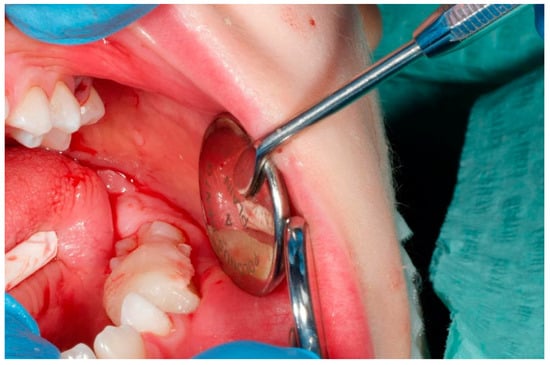

2. Case Report